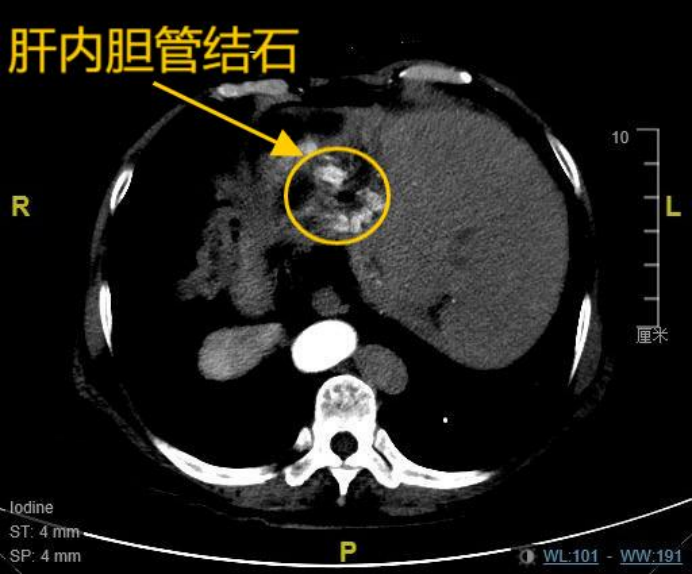

患者韩女士(化名),67岁,8年前因胆总管结石、胆囊结石曾接受传统开腹手术,术后三年结石复发,导致其长期饱受肝内胆管结石困扰,反复发作的右上腹疼痛严重影响了她的生活质量。更为特殊的是,韩女士存在罕见的全内脏反位,即医学上所指的“镜面人”,她的心脏、肝脏、脾脏等脏器均与正常解剖位置呈镜像反位分布,这是一种罕见的内脏解剖变异,发生概率约万分之一,这为手术操作带来极大挑战。8年前,由于特殊的身体情况,其开腹手术曾耗时长达10小时。近期复查的肝胆CT提示:肝内胆管多发结石伴肝左叶萎缩,肝总管及部分二级胆管扩张。面对多家医院“需再次开腹”的诊疗建议,患者坚持寻求微创解决方案,最终慕名求诊于ac米兰官网中文网站一院肝脏微创外科麻勇主任团队。